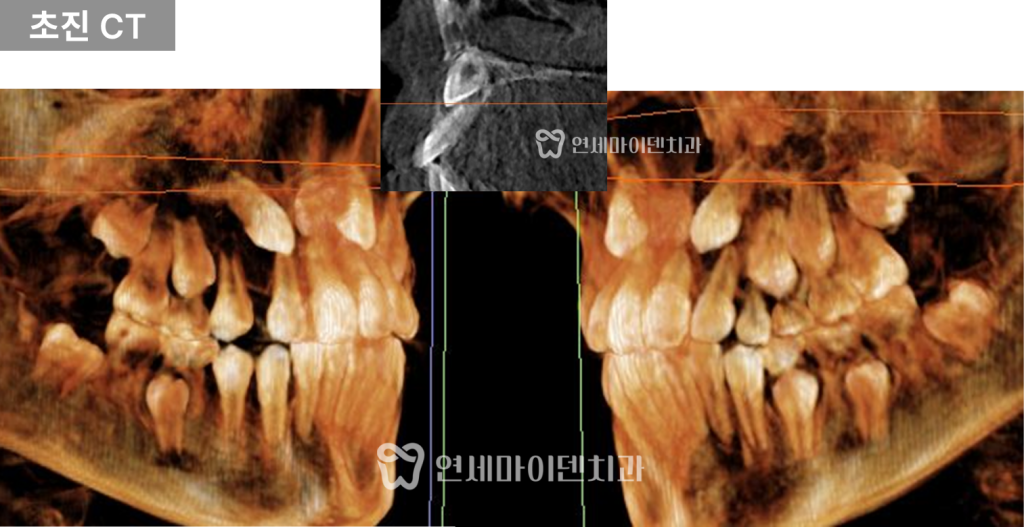

치료계획: 성장단계 고려, CT 정밀 진단

해당 환자분은 성장기 어린이였기 때문에

정확한 진단을 위해 다음 항목을 함께 확인했습니다.

- 손뼈 X-ray: 성장 속도 및 성장판 성숙도 평가

- CT: 매복 송곳니의 정확한 위치, 방향, 주변 치아 뿌리와의 거리 확인

진단 결과

- 오른쪽 송곳니:

공간만 확보한다면 자발적인 맹출 가능성이 높았습니다. - 왼쪽 송곳니:

위치가 치열 바깥쪽 전방에 있어

자연적으로 내려오기는 어려운 상태였고,

수술적 견인이 필요한 것으로 판단되었습니다.